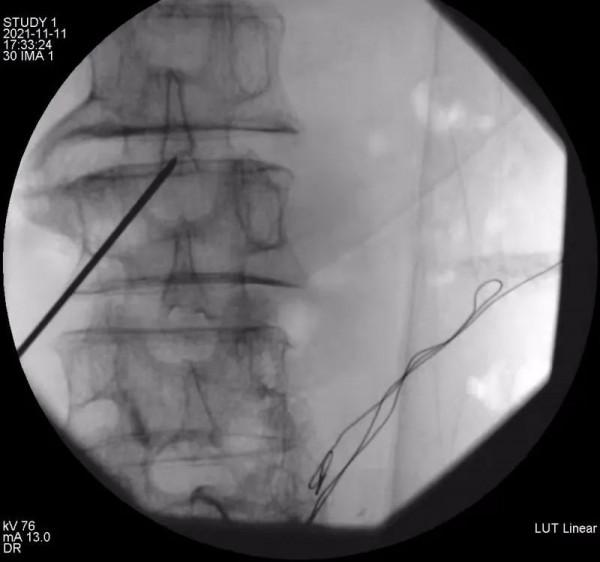

11月9日上午,餘斌教授為還先生進行了鎮痛泵安裝前鞘內嗎啡測試,結果顯示鞘內嗎啡對患者的鎮痛效果十分明顯。家屬決定正式安裝鞘內鎮痛泵。11月11日下午,餘斌教授經過仔細評估和精心準備後,會同新華醫院馬柯主任、同濟醫院骨科樊健主任、蔡濤醫生一起,為還先生成功實施了該手術。術後鎮痛效果良好,當晚還先生就沒有了疼痛的折磨,VAS評分降至3分以下。自嗎啡泵植入後,每天僅需嗎啡0.4mg即可達到滿意鎮痛效果,阿片類藥物副作用明顯減少。解決了疼痛,患者的睡眠、飲食和精神狀態都得到了極大的改善。